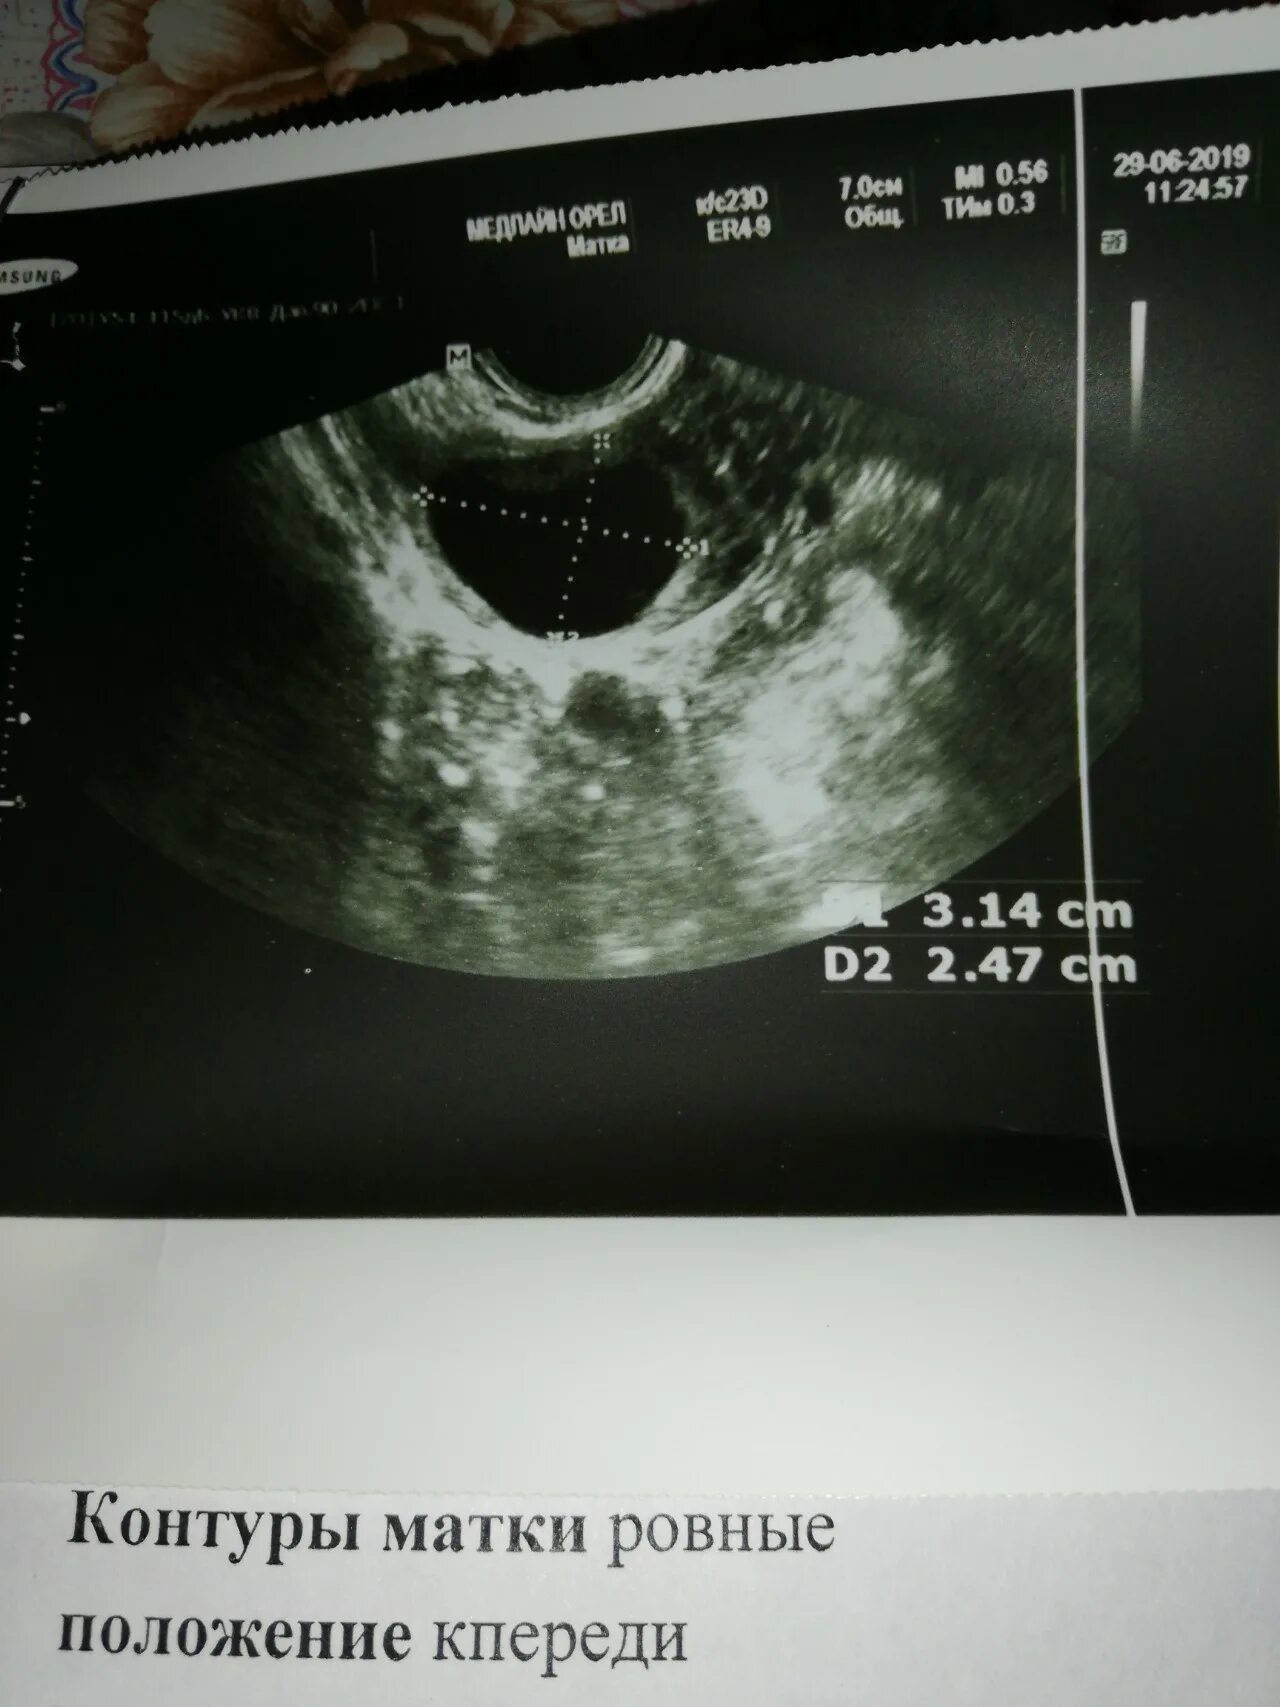

Киста уменьшается в размере